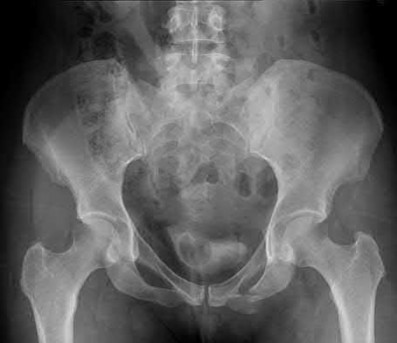

The image shows a reverse obliquity intertrochanteric hip fracture.

According to the referenced article by Haidukewych et al, unstable peritrochanteric hip fractures have a worse outcome (failed in 9/16 cases) if treated with a sliding hip screw. Two additional factors that were found to have a strong correlation with postoperative failure (nonunion, loss of reduction) were poor reduction and poor implant placement. In this study, fixed angle devices were superior. Intramedullary fixation has the added advantage of a shorter lever arm and less potential for fracture collapse and limb shortening.

The IMN also acts as a medial buttress.

According to Sanders et al, the dynamic condylar screw (DCS) can also be used in subtrochanteric models, but should not be used if extensive comminution is seen, as they reported a high failure rate with DCS in these fractures if highly comminuted. They report a 77% overall union rate with this device.